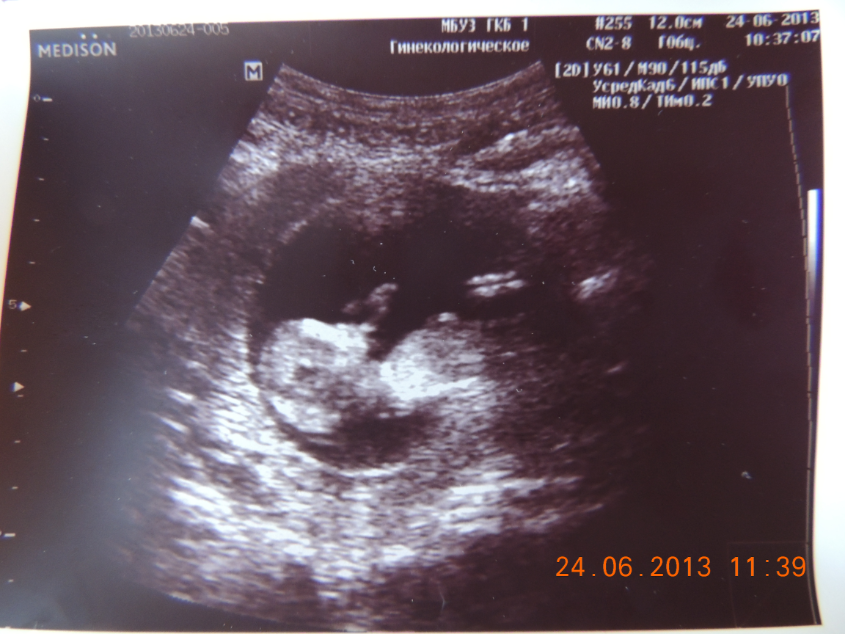

12 недель. УЗИ =)

Дождалась я 12 недельки и узи, наконец-то

По результатам узи все хорошо: Плод один, отслойки, тонуса нет, яйцо не уплощено. Плацентация по передней стенке (вот не помню, как с Маришкой было, надо было записывать). КТР 55.4, по таблице должен быть 47, длинненький какой ))) Сердечная, двигательная активность + (сказала, что крутится очень, Маринка моя не крутилась так, про гипоксию ничего не сказали). Вор. пр-во - 2,44 мм. Кровь сдала тоже сегодня, меня любят в ЖК )))) Ждем результата и на прием 27 числа теперь

Ну и Фото

Головастик такой смешной

А-ха-ха-ха ))))))) Маш, насмешила )))))))) Позирует, его еле поймали ))))))))